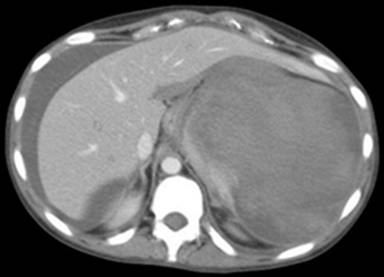

The patient self-discharged from the hospital against medical advice the day following admission, but required emergency readmission seven days later with increasing epigastric and left upper quadrant pain, fever and tachycardia. Her serum amylase was 135 U/L and white cell count was elevated at 39.1 x109/L. A repeat CT scan showed splenic vein thrombosis and disruption of the spleen which is shown in Figure 4.

Figure 4. Splenic rupture (Case #2). |

She underwent splenic artery embolisation prior to surgery and at operation was found to have a large haematoma with blood and clots in the lesser sac with a thin rim of identifiable splenic tissue which was bleeding. This was excised to obtain haemostasis. Post operatively her drain fluid was high in amylase (29,000 U/L) signifying a pancreatic fistula which dried up in five weeks.